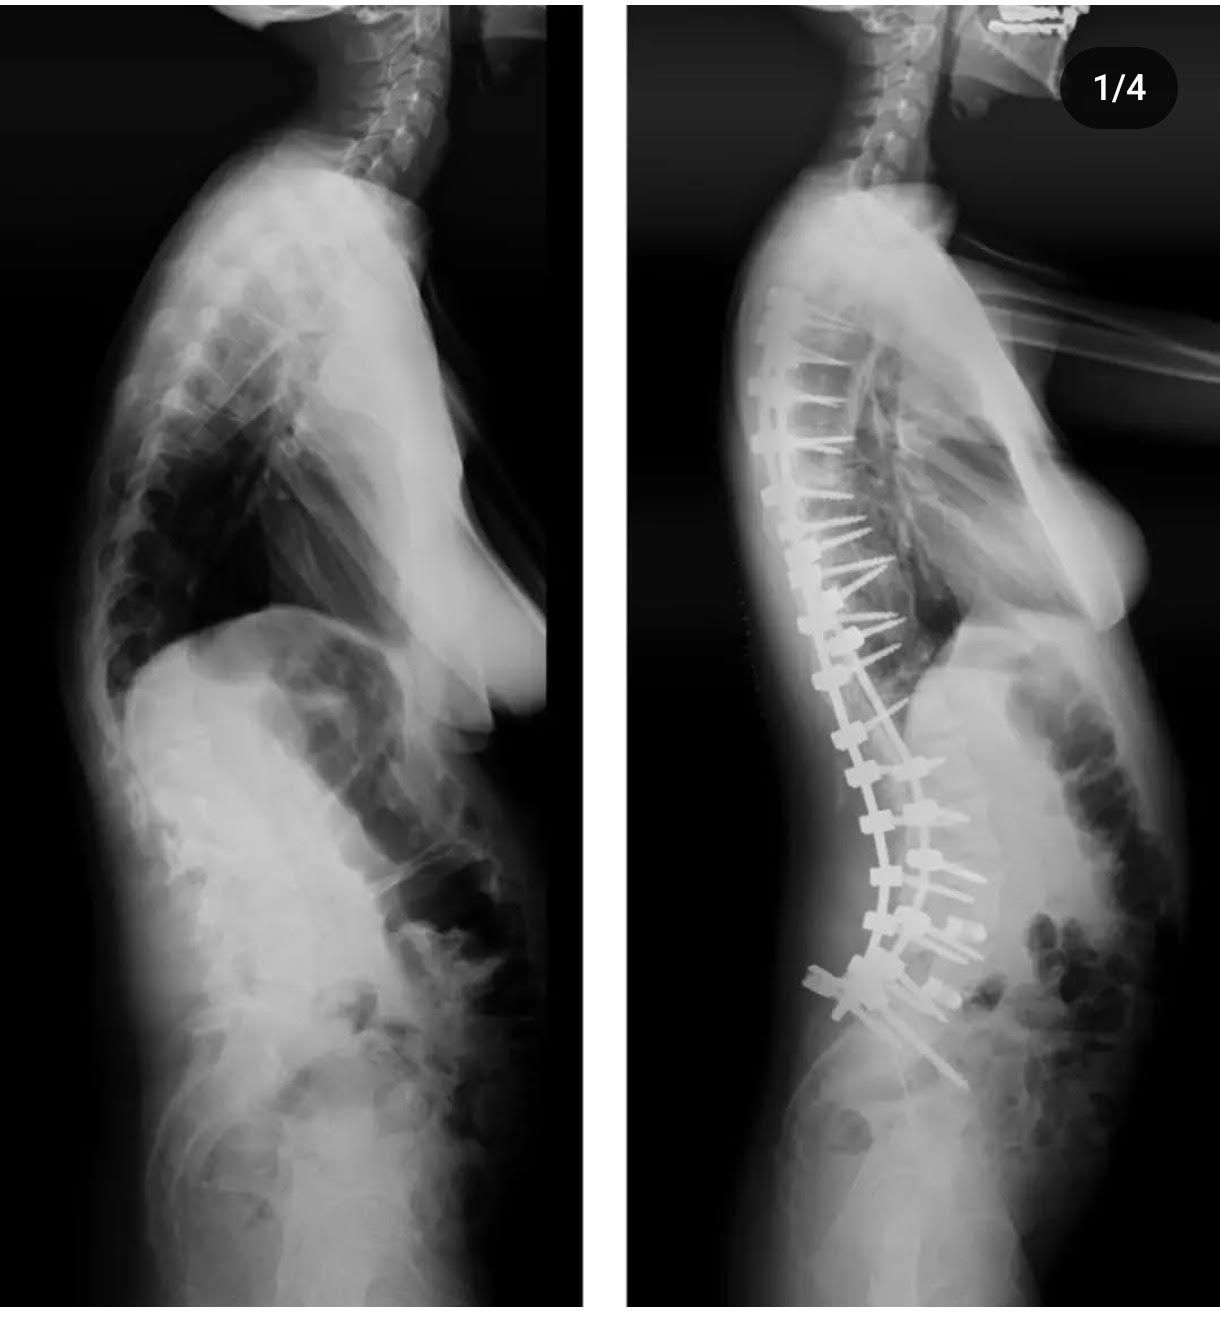

Revision surgery refers to a second intervention on the spine, performed when a previous surgery has not given the expected results or has generated complications.

To address these situations, it is essential to have a multidisciplinary team, perform all the necessary tests and examinations, and carefully plan a surgery that offers definitive and satisfactory results for the patient.

Revision surgery is a complex procedure that requires highly experienced surgeons specialized in this type of surgery. interventions.